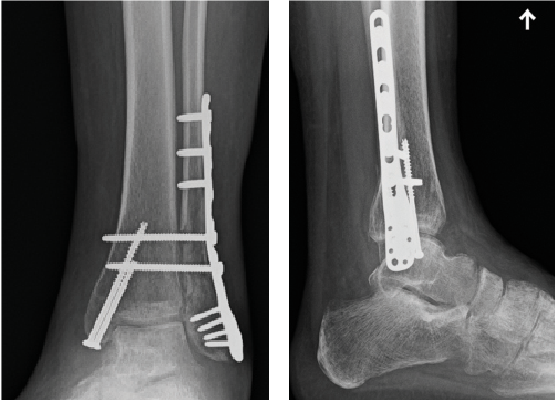

The patient is a 38-year-old opioid-naïve woman with no other significant past medical history who suffered a closed, left bimalleolar fracture with syndesmotic disruption in December 2017 when she slipped on ice and fell. She had no other injuries at the time. The patient went to the emergency department on the day of injury and was close reduced and splinted. She had open reduction internal fixation (ORIF) of the distal fibula with a lateral locking plate, cannulated screw fixation of the medial malleolar fracture and syndesmotic screw fixation eight days after injury when her swelling was improved.

The patient was non-weightbearing in a splint postoperatively. She received a popliteal and saphenous block by anesthesia preoperatively. We utilized our aforementioned protocol to manage her postoperative pain, again emphasizing scheduled non-narcotic medications and incorporating opioids only as necessary for breakthrough postoperative pain. At her first postoperative visit 13 days later, she reported adherence with her postoperative medication instructions. We had prescribed 30 tabs of oxycodone per our rearfoot and ankle protocol, and she used 18 tabs. The patient reported that she did not need oxycodone beyond postoperative day four. She went on to heal her fracture uneventfully and transitioned to pain-free weightbearing in regular shoe gear at 12 weeks post-op.